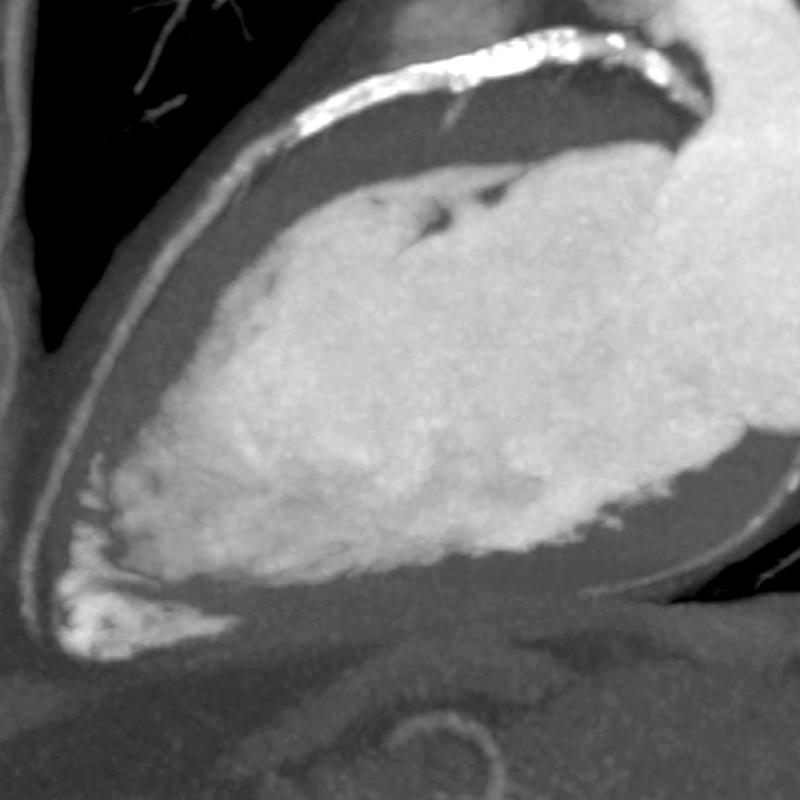

Severe coronary calcification influences the effectiveness of coronary CTA in ruling out CAD. Frequently these patients are referred for invasive angiography because of clinical suspicion of significant CAD. Stents placed in the coronary arteries can make visualization of the lumen within the stent difficult, hindering the ability to diagnose in-stent restenosis. SURE Subtraction Coronary removes calcification and stents from the coronary arteries, therefore improving visualization of the coronary lumen. Blooming effects caused by calcification are dramatically reduced.

An added benefit of SURE Subtraction Coronary is that it can be obtained with a near-dose-neutral scanning protocol. Coronary Subtraction is performed by subtracting a routine calcium score dataset from a coronary CTA dataset, the calcium score scan being used as the non-contrast mask for subtraction. Atlas-based cardiac segmentation and sophisticated rigid and deformable registration algorithms enable accurate subtraction of the coronary arteries to become a reality, leading to improved visualization of the coronary lumen.